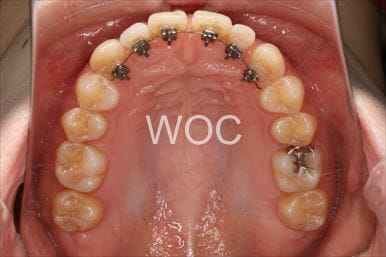

治療後1

治療後2

治療後3

治療後4

治療後5